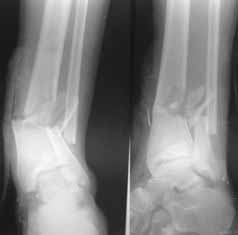

Male 22 yrs of age, RTA, front seat passenger in a truck. Sustained grade IIIB fracture of Tibia, and a Posterior dislocation of the Ipsilateral Left Hip.

Emergent closed reduction performed, and Tibial wound debrided. Next day Exfix applied and fibula plated. Initially femoral head fracture was not appreciated and it was thought that this is a posterior wall fracture. Presently two weeks down the line, Tibial wound is better but not completely healthy. and plastics want to wait for another five days, before they flap it. I enclose radiographs, Judet view, Ct scans in this and following mails.

Based on the selected images that you shared with us, I would not leave it as is. The fragment is significant in terms of its size and location and displacement.